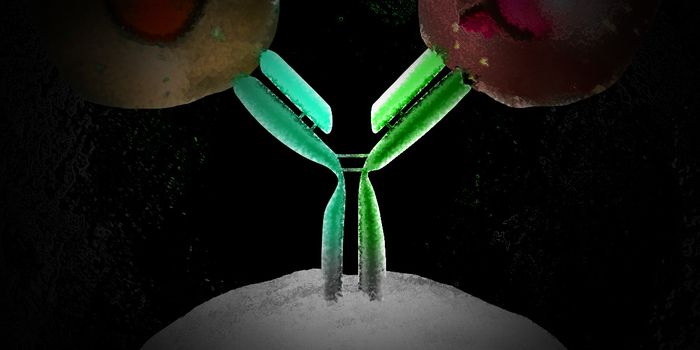

APR 11, 2023CancerMonoclonal antibodies have revolutionized cancer therapy since their introduction as therapeutics in the field. To enhan ...

MAR 21, 2023Drug Discovery & DevelopmentTherapeutic antibodies are one of the best-selling drug classes in the pharmaceutical market, and the advent of antibody ...

JUL 18, 2023Drug Discovery & DevelopmentEvolution of Antibody Humanization and Affinity Maturation Antibodies play a vital role in the immune system by providin ...